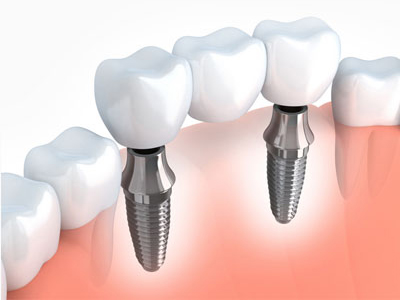

Single Tooth Implant

Replaces one missing tooth in a fixed and secure way.

Multiple Implants

Restore several teeth while maintaining chewing function and jaw health.